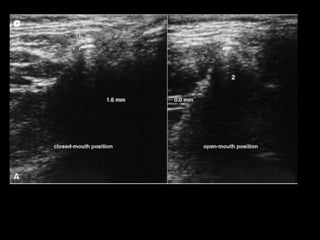

 Ultrasonography uses sound waves of high

frequency to produce images of body.

 Scanning transducer of 7.5-12 MHz is used

 Depicts narrow space of joint

 Position of disc

 Fluid and ligament adhesion

 Transducer is placed on skin above joint parallel to long

axis of mandible

 Disc seen as thin homogenous hypoechoic areas

 Condylar borders and Articular eminence shows a

hyperechogenic lines

 it is possible to directly observe the joint disc

movement, when the mouth is opening and closing

linear transducer positioned against the patents face in a horizontal direction overlying

the zygomatic arch and t.m.j. & 25° to mid sagittal plane